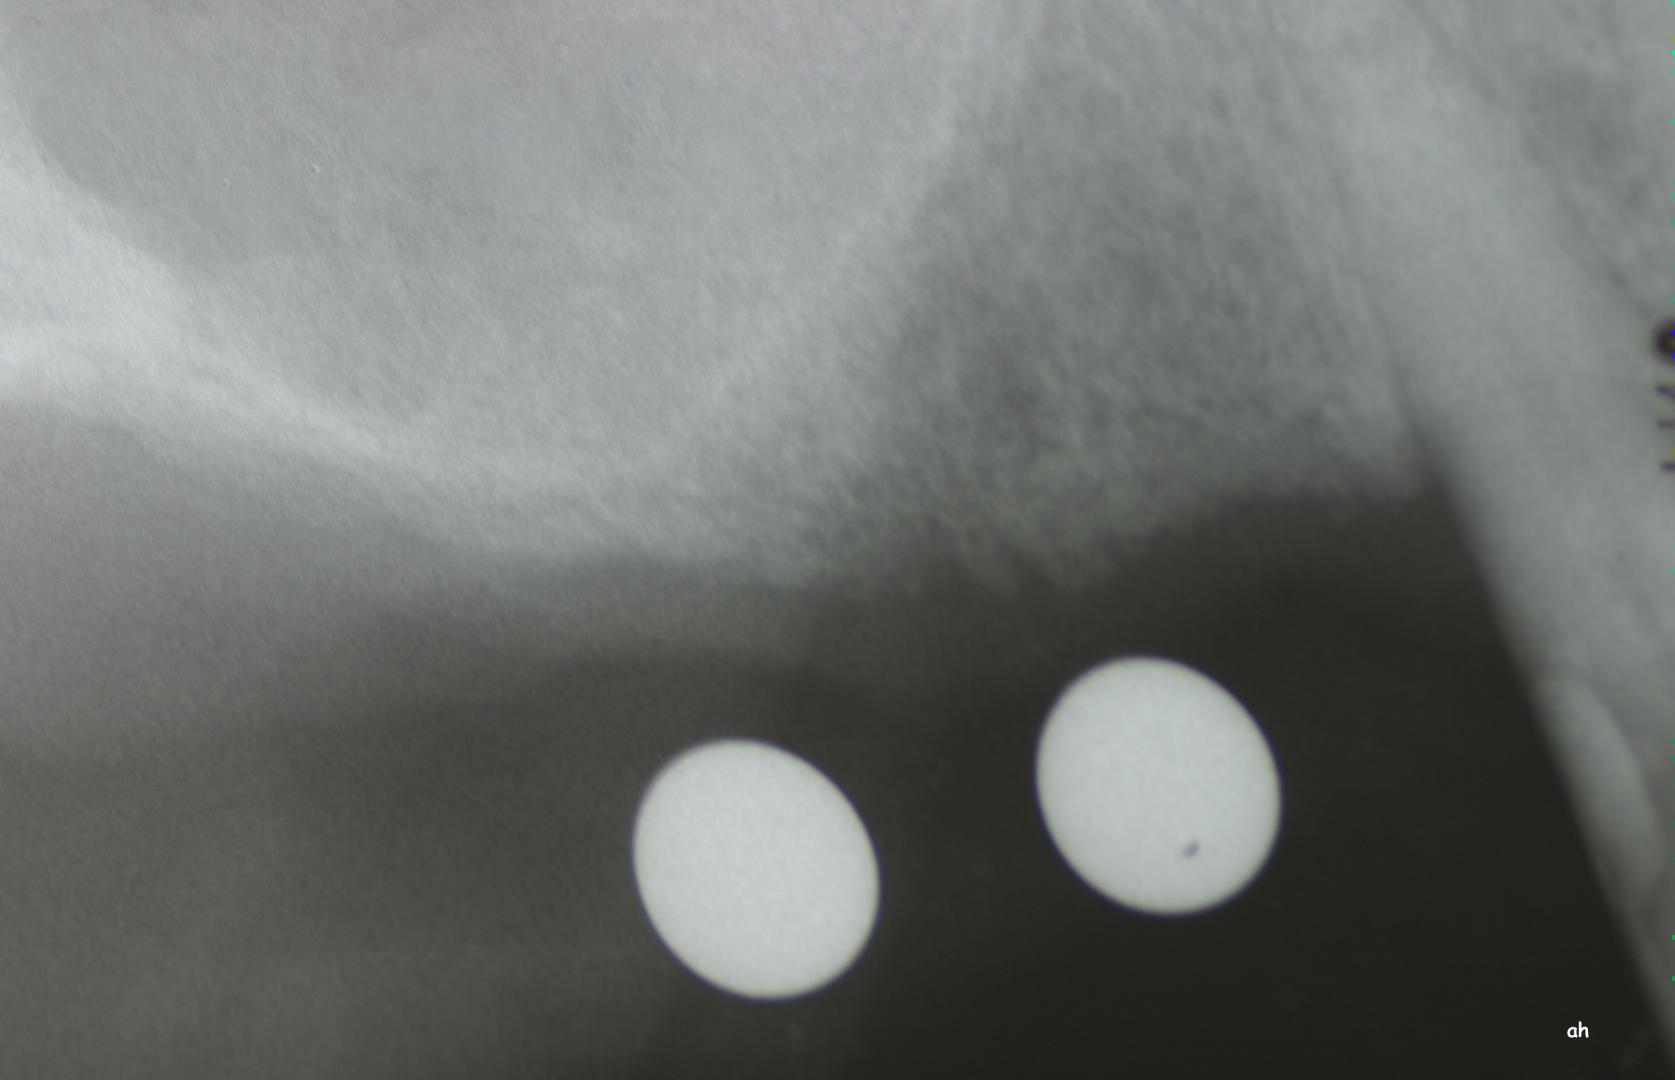

Exemple 12: Ici la pose de deux implants est envisagée, mais la hauteur d'os est insuffisante pour le deuxième implant. Le sinus (qui est une cavité creuse) est à moins de 6 mm de la surface de l'os. Idéalement il faudrait 10 mm d'os.

Exemple 12: Il faut donc relevé le sinus avec une greffe d'os avant de poser l'implant (Sinus lift).